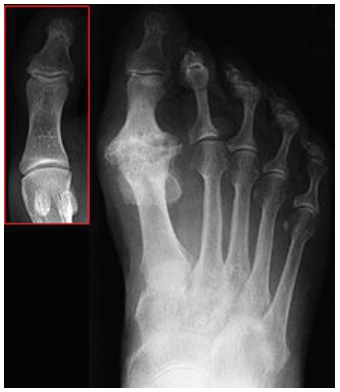

Arthritis (wear and tear) is the most common cause of hallux rigidus. The arthritis develops in the joints at the base of the big toe, and is caused by the wearing out of the joints surfaces. This can develop in people of all ages.

With this condition you can develop inflammation and stiffness, leading to reduced mobility of the big toe causing pain in the joint and the ball of the foot.

With a minimally invasive cheilectomy a 3mm cut is made into the side of the big toe. Through this cut the surgeon is able to remove the ridge of bone by using a very small drill called a burr. This is done under x-ray guidance.